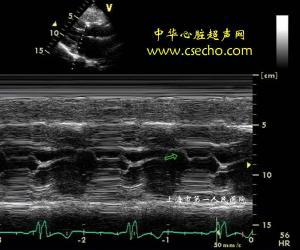

超声可以评估二尖瓣前叶的活动,反应sam征,以了解左室流出道梗阻情况

5,收缩期可见二尖瓣前瓣前向运动,即sam征,部分患者可因此合并二尖瓣

5 平方厘米 室间隔明显增厚者,二尖瓣可出现sam征,心尖区可闻及收缩

二尖瓣sam征M型示意图